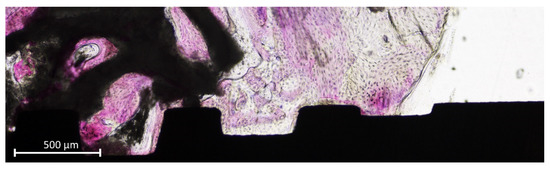

High light intensity was provided to better identify this structure (Figure 6a–d).

Figure 6.

(a–d) Photomicrographs representing new bone and interpenetrating bone network (IBN). (a,c) Dark mode, at which a normal light exposure was adopted. (b,d) Overexposed images that better revealed the structure of the IBN.

In the present study, the term “interpenetrating bone network (IBN)” was used. This term was first used in an experimental study in which a biphasic biomaterial, composed of 60% hydroxyapatite (HA) and 40% of beta-tricalcium phosphate (β-TCP), was used as filler material for sinus augmentation in rabbits [55]. Providing a higher light intensity at the optical microscope, it was possible to identify new bone overlapping or within the graft residues (Figure 6a–d). This was shown also in another previously published article on sinus floor elevation in sheep in which a biphasic biomaterial was also used as filler, again composed of HA 60% and β-TCP 40% [56]. The structure of the IBN recalled the structure of an “interpenetrating polymer network” [57] and, for this reason, the term “interpenetrating bone network” was adopted.